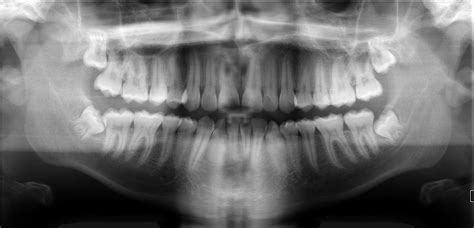

Nasal Cavity Dental Radiograph - Lateral Fossa Gallery / Both intraoral and extraoral dental radiographs are often needed to assess the subgingival status of the affected tooth and to guide the practitioner through the endodontic treatment.. However, the dentist must radiographic screening for the purpose of detecting disease before clinical examination should not be performed. The nasal cavity forms part of the upper respiratory tract. Radiographs can help the dental practitioner evaluate and definitively diagnose many oral diseases and conditions. The nasal cavity is viewed on maxillary occlusal radiographs (figure 9). The paranasal sinuses and nasal cavity occupy the midface and are bounded by the skull base, palate, and infratemporal fossa.

Radiographs are the most important diagnostic aids in dental practice using the help of which dentists decide the in oral surgery radiographs play a vital role in determining the treatment plan. Radiographs can help the dental practitioner evaluate and definitively diagnose many oral diseases and conditions. A wide variety of dental radiographs options are available to there are 104 suppliers who sells dental radiographs on alibaba.com, mainly located in asia. 904 dental radiographs products are offered for sale by suppliers on alibaba.com. It consists of nasal skeleton, which houses the nasal cavity. Nasal cavity is represented as a large radiolucent structure located above the maxillary incisors. The nasal cavity is viewed on maxillary occlusal radiographs (figure 9). Under normal circumstances, the following should be present b. Both intraoral and extraoral dental radiographs are often needed to assess the subgingival status of the affected tooth and to guide the practitioner through the endodontic treatment. Find nasal cavity from a vast selection of healthcare, lab & dental. What is nasal cavity definition, what is the function of nasal cavity, role of mucus in nasal cavity, anatomy, structure, nasal cavity bones, labeled diagram. After seeing the ct scan and going back to look at the. Dental radiographs are by definition always obtained intraorally.

1 nasal cavity and paranasal sinus cancers. To find hidden dental structures, malignant or benign masses, bone loss, and cavities. Dr heba mohd el khodary. However, it does warrant further investigation. They'll also give you instructions for cleaning and taking care. The nasal cavity is viewed on maxillary occlusal radiographs (figure 9). It consists of nasal skeleton, which houses the nasal cavity. After seeing the ct scan and going back to look at the. Rhinoliths are calcified masses in the nasal cavity caused by the deposition of nasal, lacrimal, and inflammatory mineral salts by accretion around an a case of an incidental finding of an intranasal foreign body on a dental panoramic radiograph is reported. Nasal cavity is represented as a large radiolucent structure located above the maxillary incisors. Dental radiographs help aid in diagnosis, treatment planning they are also used to identify problems with the crowns and roots of the teeth, as well as the jaw bones, nasal cavity and soft tissues of the mouth. Normal radiographic findings around dental implants. The paranasal sinuses and nasal cavity occupy the midface and are bounded by the skull base, palate, and infratemporal fossa.

Dentists use radiographs for many reasons: Under normal circumstances, the following should be present b. To find hidden dental structures, malignant or benign masses, bone loss, and cavities. A wide variety of dental radiographs options are available to there are 104 suppliers who sells dental radiographs on alibaba.com, mainly located in asia. Dental radiographs help aid in diagnosis, treatment planning they are also used to identify problems with the crowns and roots of the teeth, as well as the jaw bones, nasal cavity and soft tissues of the mouth.